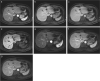

Gadolinium ethoxybenzyl diethylenetriamine pentaacetic acid (Gd-EOB-DTPA; Gadoxetic acid; Gadoxetate disodium) is a hepatocyte-specific MR contrast agent. It acts as an extracellular contrast agent in the early phase after intravenous injection, and then is taken up by hepatocytes later. Using this contrast agent, we can evaluate the hemodynamics of the liver and liver tumors, and can therefore improve the detection and characterization of hepatocellular carcinoma (HCC). Gd-EOB-DTPA helps in the more accurate detection of hypervascular HCC than by other agents. In addition, Gd-EOB-DTPA can detect hypovascular HCC, which is an early stage of the multi-stage carcinogenesis, with a low signal in the hepatobiliary phase. In addition to tumor detection and characterization, Gd-EOB-DTPA contrast-enhanced MR imaging can be applied for liver function evaluation and prognoses evaluation. Thus, Gd-EOB-DTPA plays an important role in the diagnosis of HCC. However, we have to employ optimal imaging techniques to improve the diagnostic ability. In this review, we aimed to discuss the characteristics of the contrast media, optimal imaging techniques, diagnosis, and applications.